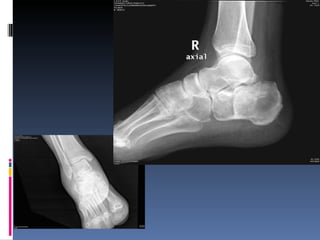

Fractura del calcaneo por insuficiencia

Fractura del calcaneopor insuficiencia